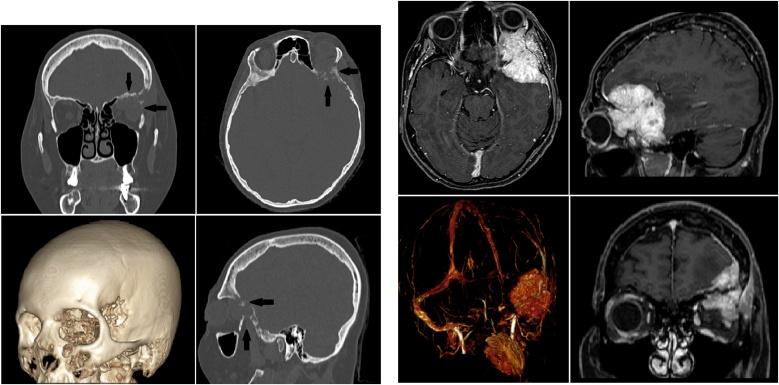

我们描述了一例复杂的额眶颅底转移瘤病例,该病例需要进行颅骨重建,我们采用单步手术和定制植入物进行治疗。我们的手术包括两个步骤:第一步,我们在先前基于高分辨率骨CT扫描构建的3D虚拟模型上进行“虚拟”开颅手术。第二步,即实际手术过程,患者接受使用定制聚甲基丙烯酸甲酯颅骨成形术植入物进行颅骨缺损的切除和重建。报告了为期三个月的临床和影像学随访情况,记录了切除范围和良好的美学效果。

We describe a single case of a complex fronto-orbital skull base metastasis requiring skull bone reconstruction that we treated with a single-step surgery and custom-made implant. Our procedure consists of two steps: in the first one, we perform a "virtual" craniotomy on a 3D phantom model previously built on a high-resolution bone CT scan. In the second step, the actual surgical procedure, the patient undergoes the resection and reconstruction of the cranial defect with an implant of PMMA custom-made cranioplasty. A three-month clinical and radiological follow-up is reported, which documented the extent of resection and good aesthetic results.

临床讨论

在我们的病例中,我们对颅眶区域进行了颅骨重建,并对肿瘤进行了大体全切。术后一个月进行了辅助放疗。三个月的随访显示美学效果良好且无疾病进展。提供了近期的文献综述以讨论不同的重建技术。